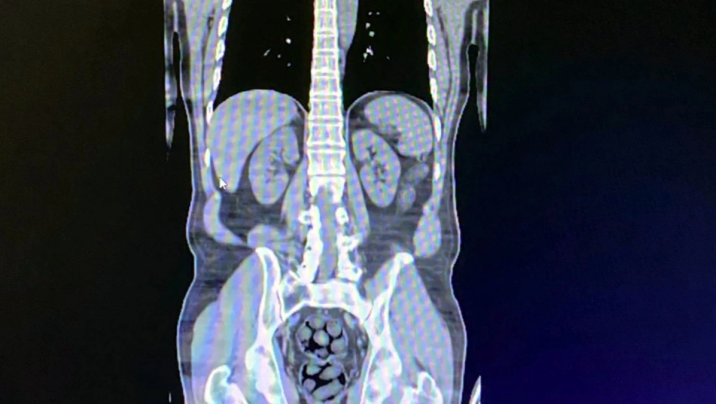

Türkiyənin Bitlis vilayətində sərnişin avtobusunda saxlanılan 3 iranlı şübhəlinin mədə və bağırsaqlarında narkotik vasitə gəzdirdiyi müəyyən edilib.

Stopnarkotik.az "Haber Global"a istinadən xəbər verir ki, şübhəlilərin daxili orqanlarından 91 paketdə 1 kilo 126 qram metamfetamin çıxarılıb.